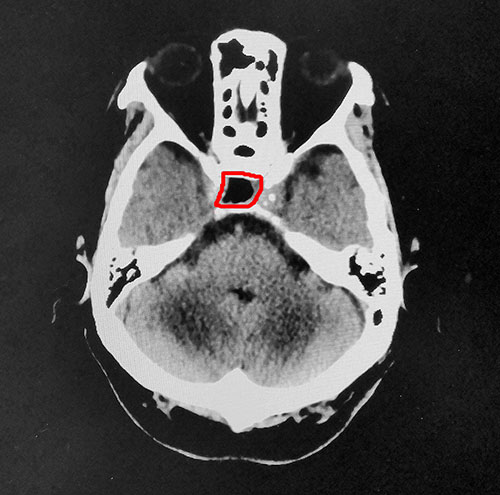

▲术后CT影像:肿瘤切除干净,鞍内脑脊液填充

整个切除手术用时不到1小时,术中出血量很少,肿瘤切除干净。术后王老伯被医护人员唤醒,被安全送到重症监护室监护。